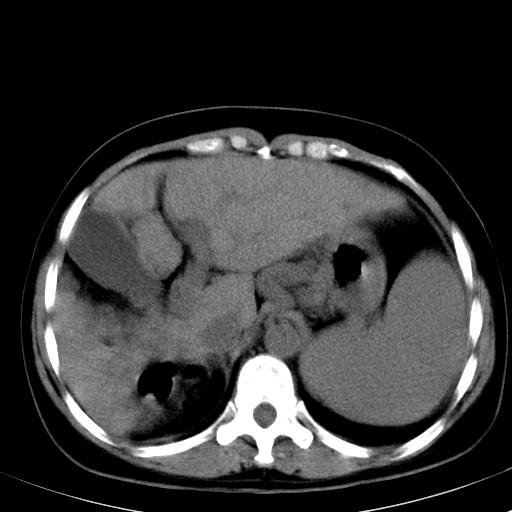

肝硬化、门脉高压、脾大。再障+肝硬化促成巨脾。

肝硬化,门脉高压,脾大。

肝硬化,门脉高压,脾大